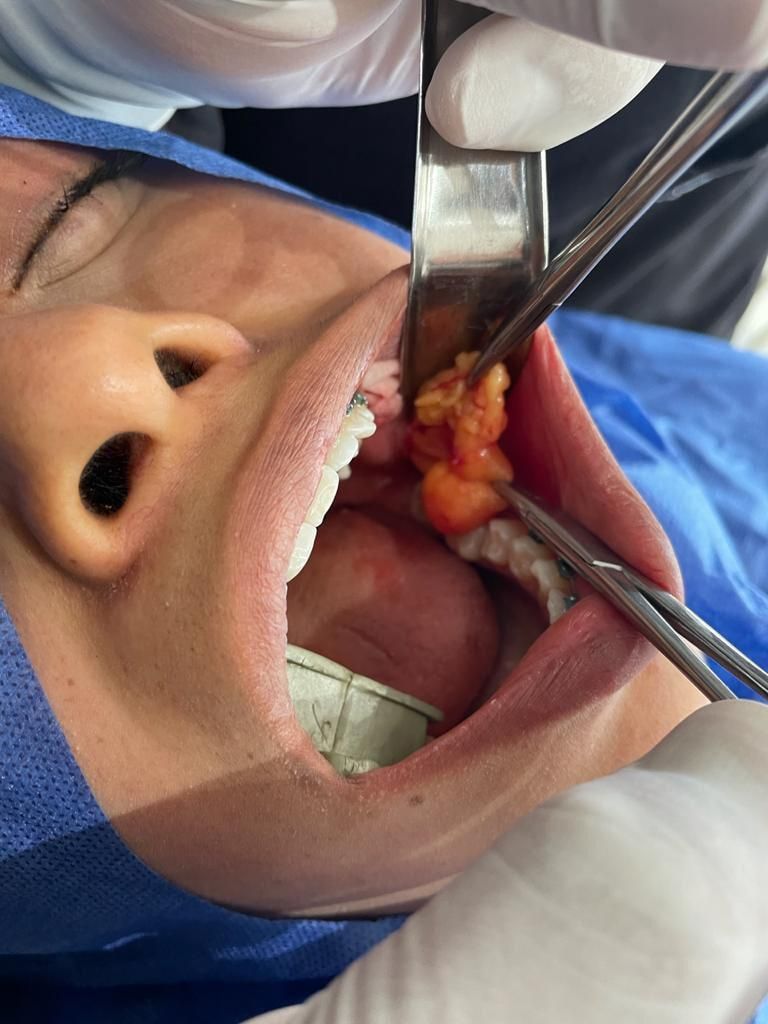

BICHECTOMÍA

Procedimiento quirúrgico en cavidad oral el cual tiene como objetivo reducción de mejillas, así como afilamiento y perfeccionamiento del rostro pronunciando pómulos. Mínimamente invasivo.

La gran mayoría de los pacientes son candidatos a este procedimiento, sin embargo, se requiere de una valoración previa ya que puedes existir ciertas exclusiones. El sexo es indistinto, tanto en hombres como mujeres los resultados pueden ser adecuados.